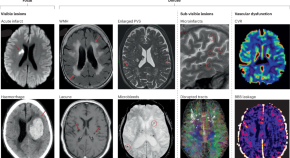

• Cerebral small vessel disease is a common cause of dementia and stroke. In this Perspective, Wardlaw and co-workers describe evidence from human brain imaging and preclinical models that points to dysfunction in the endothelial cells that line the walls of cerebral blood vessels as a key driver of small vessel disease.